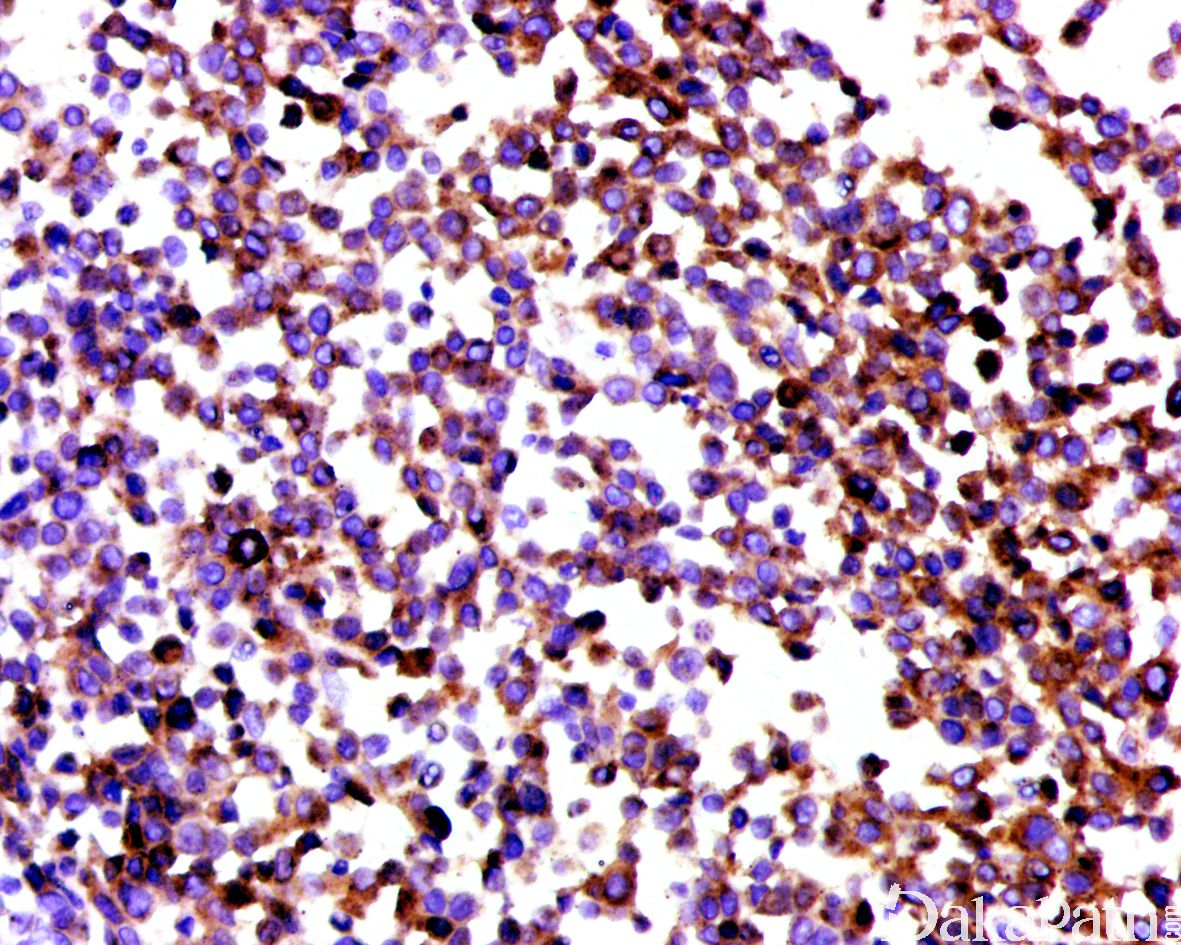

浆细胞样尿路上皮癌与普通的尿路上皮癌具有相似的免疫表型特征表达 GATA3(80%),P63(45%),CK7( 92%),CK20(70%)。由于 CDH1 基因突变,浆细胞样尿路上皮癌常出现 E-cadherin 表达缺失。少数可表达 GCDFP15,PR,CDX2 等。部分可表达 CD128,需要与浆细胞瘤鉴别,但不表达 CD38 和 MUM1 等浆细胞标志物。

淋巴瘤 和浆细胞肿瘤 :浆细胞样尿路上皮癌多数仔细寻找总能找到原位或普通的浸润性尿路上皮癌成分,需要注意的是浆样尿路上皮癌可表达 CD138,易与浆细胞瘤混淆,免疫组织化学染色上皮标记阳性等可与淋巴瘤及浆细胞肿瘤鉴别。